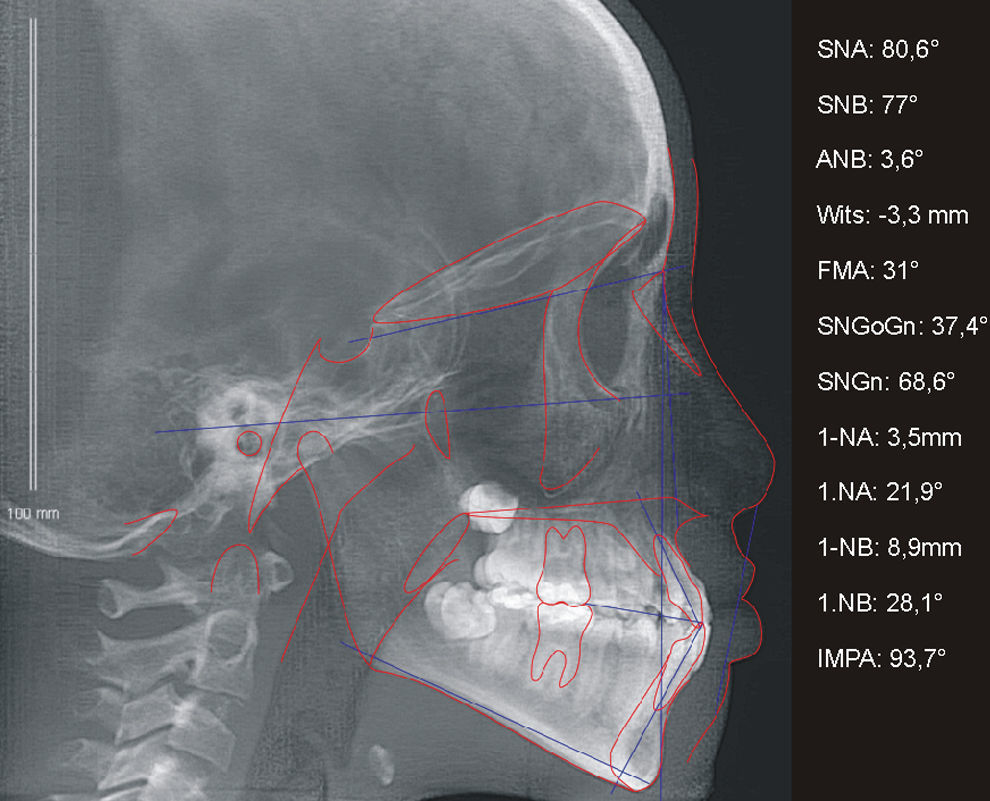

A paciente A, do sexo feminino, passou por procedimentos cirúrgicos condizentes ao protocolo de reconstrução da fenda labiopalatina na primeira infância, como queiloplastia, palatoplastia e faringoplastia12. Como esperado, houve redução da largura do arco dentário superior devido à junção dos segmentos e uma limitação no crescimento do terço médio da face. Aos 12 anos, em estágio pré‐puberal, CS1 de maturação óssea13, a paciente apresentava clinicamente um perfil côncavo, molares com padrão de oclusão em Classe I de Angle, atresia transversal maxilar severa na região anterior e mordida cruzada anterior (figs. 1 e 2). Pelo exame da telerradiografia em norma lateral da face, observou‐se a sugestão de estreitamento e constrição das vias aéreas, relação esquelética de Classe I (ANB=3,6°), mas apresentando uma tendência à Classe III (Wits=−3,3mm), maxila retroposicionada em relação à base do crânio (SNA=80,6°), bom posicionamento de incisivos superiores (1.NA=3,5mm; 1.NA=21,9°) e projeção vestibular de incisivos inferiores (1.NB=8,9mm; 1.NB=28,1°; IMPA=93,7°) (fig. 3). Como parte da documentação ortodôntica inicial para o planeamento do tratamento, que incluía os enxertos ósseos na região da fenda, a paciente foi submetido a uma tomografia computadorizada por feixes cônicos (TCFC), no tomógrafo i‐CAT (Imaging Sciences International, Hatfield, Pennsylvania, Estados Unidos da América [EUA)), com field of view (FOV) de crânio estendido (23cmx17cm), voxel de 0,3mm3, 36,90mA, 120kV e tempo de exposição de 40 segundos. Frente a todas as características encontradas, foi determinada uma maior necessidade de ERM na região anterior, em preparação para enxerto ósseo e tratamento ortodôntico corretivo. Após o diagnóstico, foi escolhido o expansor em leque. O aparelho foi confeccionado com um parafuso expansor em leque (Morelli, Sorocaba, São Paulo, Brasil). O aparelho possui bandas nos primeiros molares permanentes e uma dobradiça na região posterior, fixada em acrílico, de onde partem extensões de fio 0,9mm, apoiadas nas superfícies palatinas dos molares decíduos ou pré‐molares. Este aparelho é considerado dentomucossuportado (fig. 4).